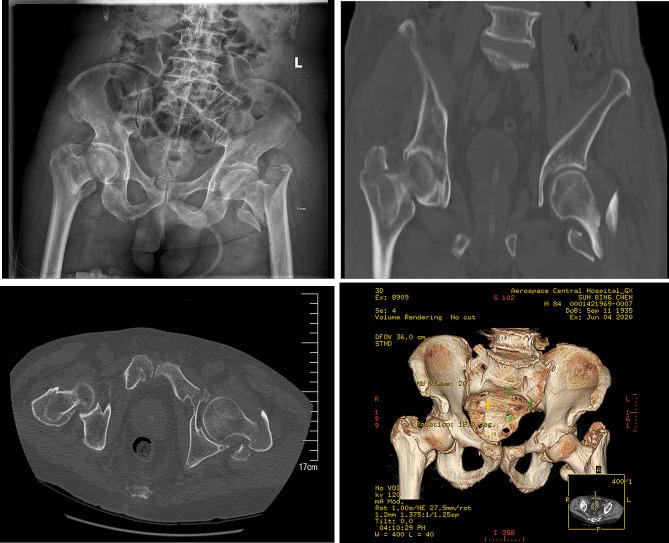

We report on an 84-year-old male who suffered severe trauma from a car accident, resulting in multiple injuries and shock state, with pain and limited mobility in both hip joints. After examination and imaging studies, the patient was diagnosed with multiple injuries and bilateral intertrochanteric fractures. Following emergency resuscitation, he was admitted to the orthopedic ward. A pre-surgical multidisciplinary team (MDT) consultation was convened to optimize surgical conditions. The patient underwent successful one-stage bilateral intramedullary nailing. The patient was assisted to stand with a walker on the third day after surgery. Six months post-surgery, the patient resumed outdoor activities.

我们报告了一例 84 岁男性患者,因车祸遭受严重创伤,导致多发伤和休克状态,双侧髋关节疼痛且活动受限。经检查和影像学研究,患者被诊断为多发伤和双侧转子间骨折。在紧急复苏后,他被收入骨科病房。为了优化手术条件,进行了术前多学科团队(MDT)会诊。患者成功接受了一期双侧髓内钉固定术。术后第 3 天,患者在助行器的辅助下站立。术后 6 个月,患者恢复户外活动。